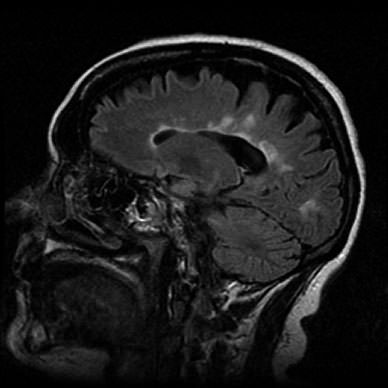

Tuttavia, unendo la risonanza magnetica ad uno speciale software, si potrebbe riconoscere la malattia in circa 10 minuti.

Il programma è stato ideato per identificare le anomalie del cervello che segnalano la presenza della patologia.

Gli studiosi l’hanno messo alla prova prendendo in esame 60 volontari:20 adulti con autismo, 20 con disturbi dell’attenzione e 20 individui autistici. Le scansioni celebrali, ottenute con la

risonanza magnetica, sono state analizzate con il software, che ha elaborato i dati ed identificato le differenze, sia a livello di corteccia celebrale che di curvatura del cervello.

Risultato: una diagnosi corretta nel 90% dei casi.